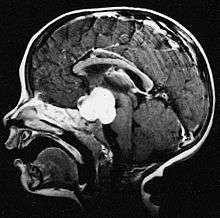

Pilocytic astrocytoma or juvenile pilocytic astrocytoma or cystic cerebellar astrocytoma (and its variant juvenile pilomyxoid astrocytoma) is a brain tumor that occurs more often in children and young adults (in the first 20 years of life). They usually arise in the cerebellum, near the brainstem, in the hypothalamic region, or the optic chiasm, but they may occur in any area where astrocytes are present, including the cerebral hemispheres and the spinal cord. These tumors are usually slow growing and benign.[1] The neoplasms are associated with the formation of a single (or multiple) cyst(s), and can become very large.

Pilocytic astrocytomas are often cystic, and, if solid, tend to be well-circumscribed. It is characteristically easily seen on CT scans and MRI.

Usually—depending on the interview of the patient and after a clinical exam which includes a neurological exam, and an ophthalmological exam—a CT scan and or MRI scan will be performed. A special dye may be injected into a vein before these scans to provide contrast and make tumors easier to identify. The neoplasm will be clearly visible.

Macroscopically, an astrocytoma is a mass that looks well-circumscribed and has a large cyst. The neoplasm may also be solid.